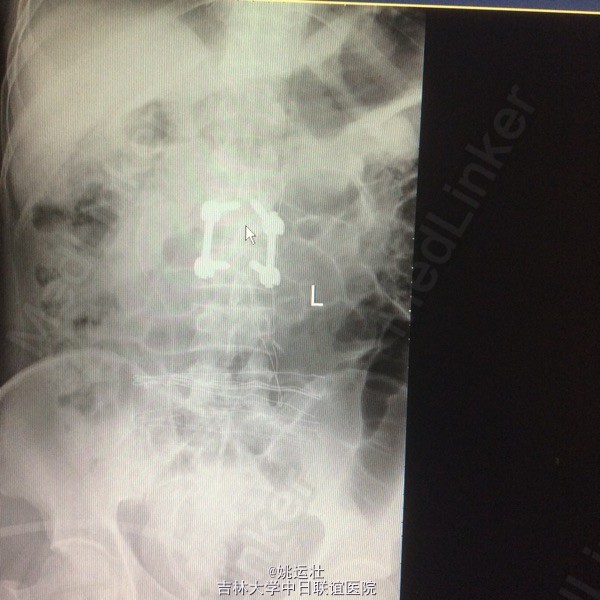

患者双下肢无明显浅感觉减退,肌力V级,肌张力不高,二便控制满意,病理征阴性。 腰椎核磁:腰1-4椎体右侧右肾下方团块状占位,大小约8#⃣6.8Cm,等T1长T2信号 腰椎Ct:占位周围见弧形钙化灶

腰椎神经鞘瘤 切除右侧横突,见腰2神经根延伸呈膜状,沿腰2神经跟出口将神经切断,完整取出肿物。